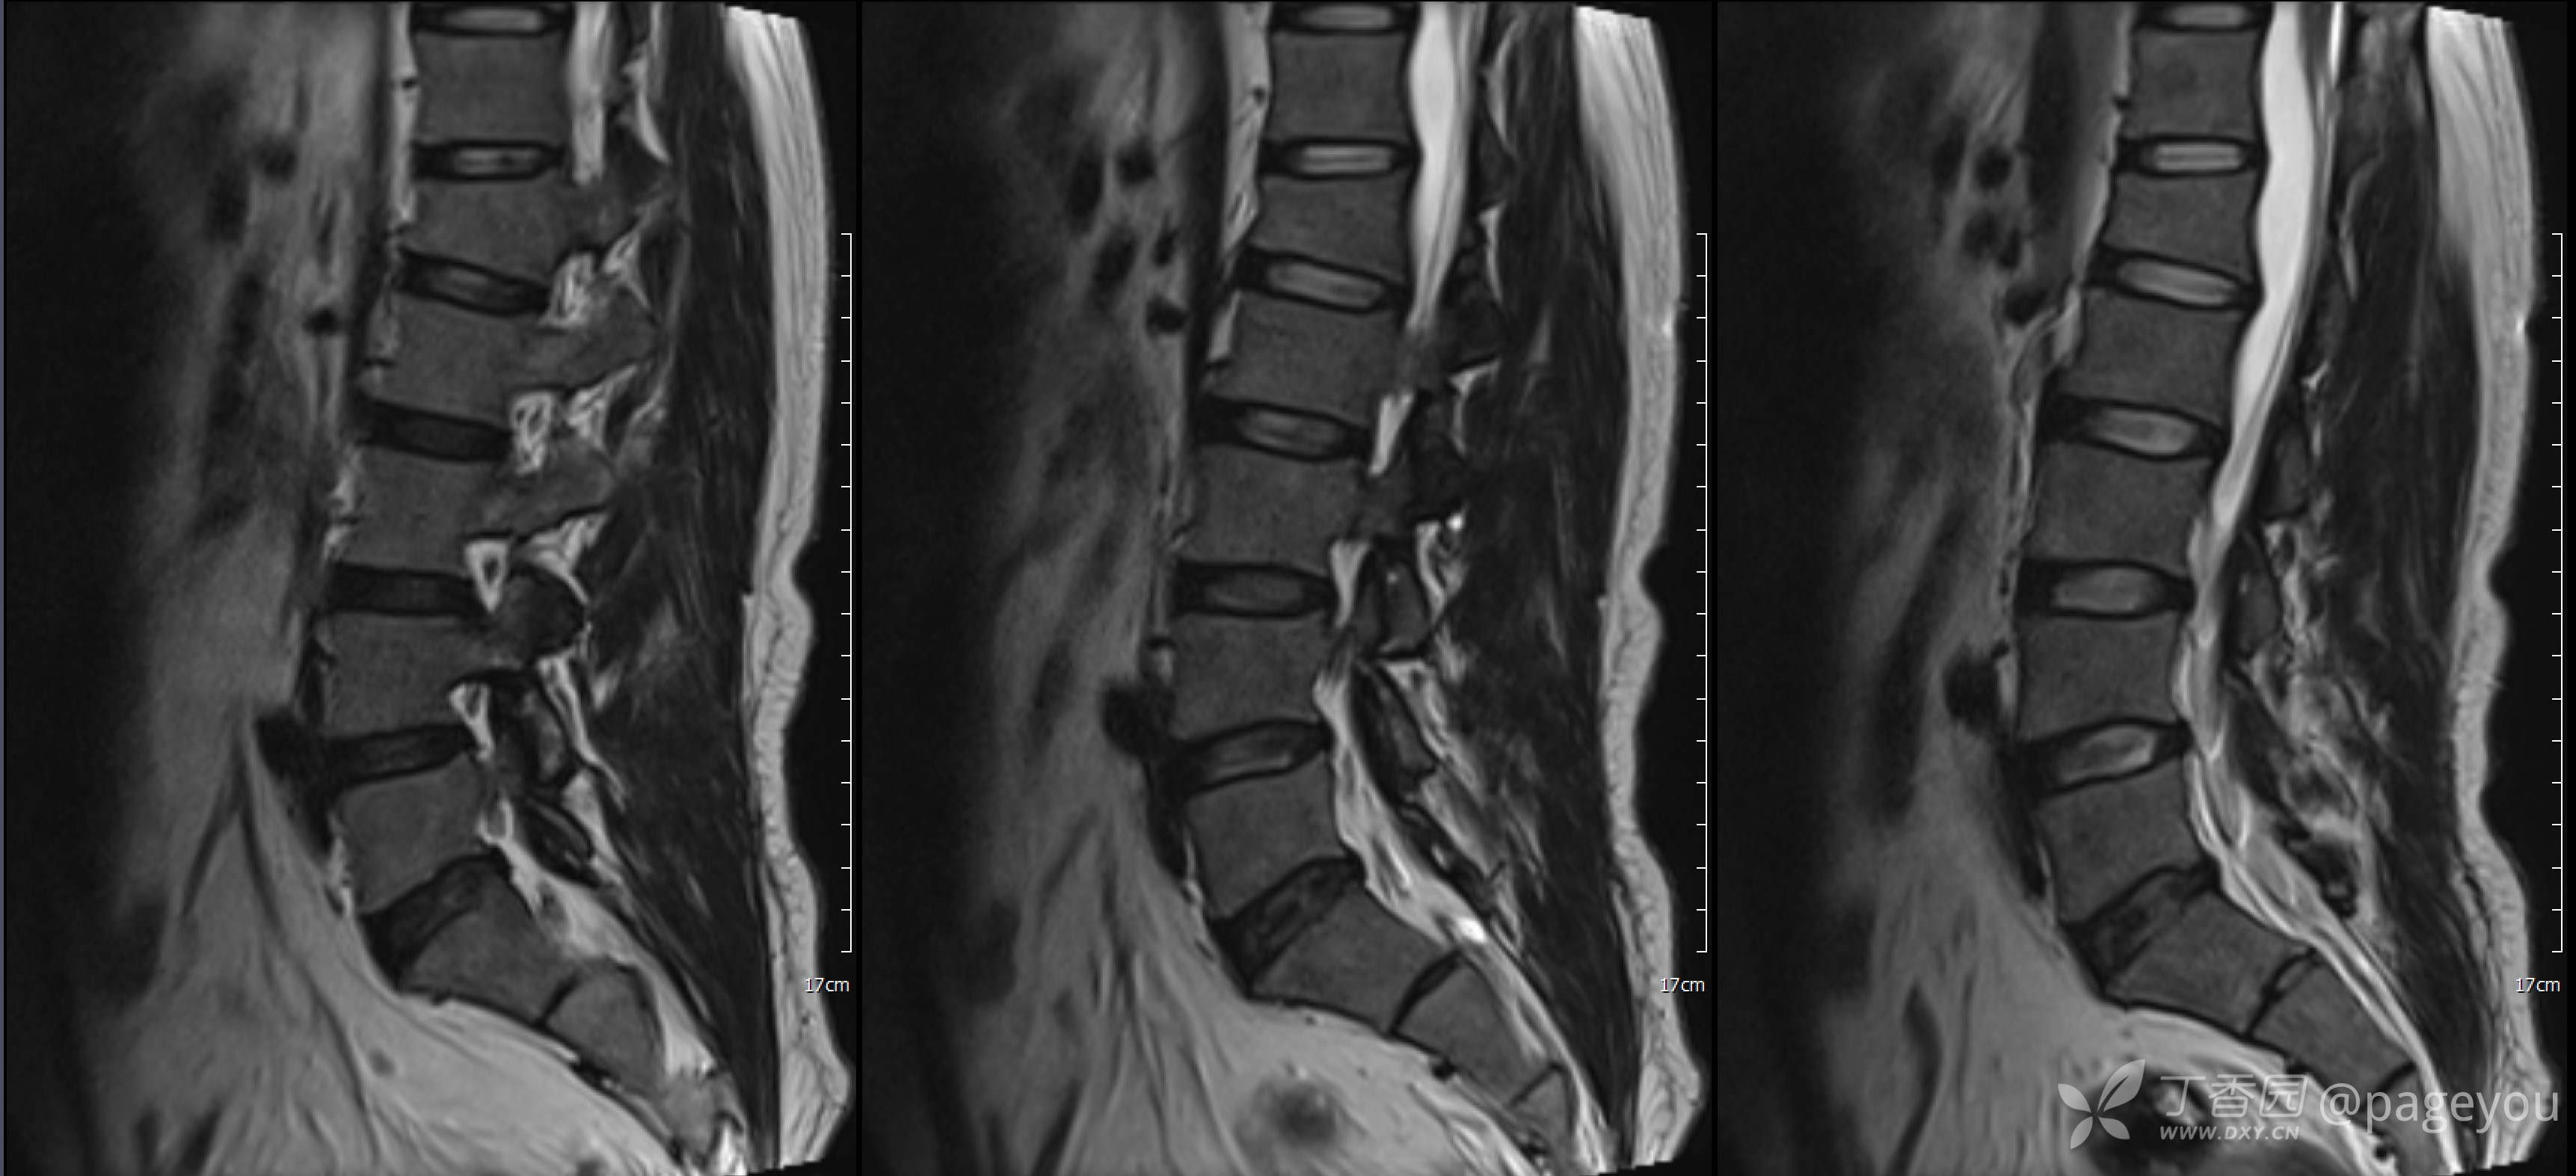

入院查腰椎MRI: